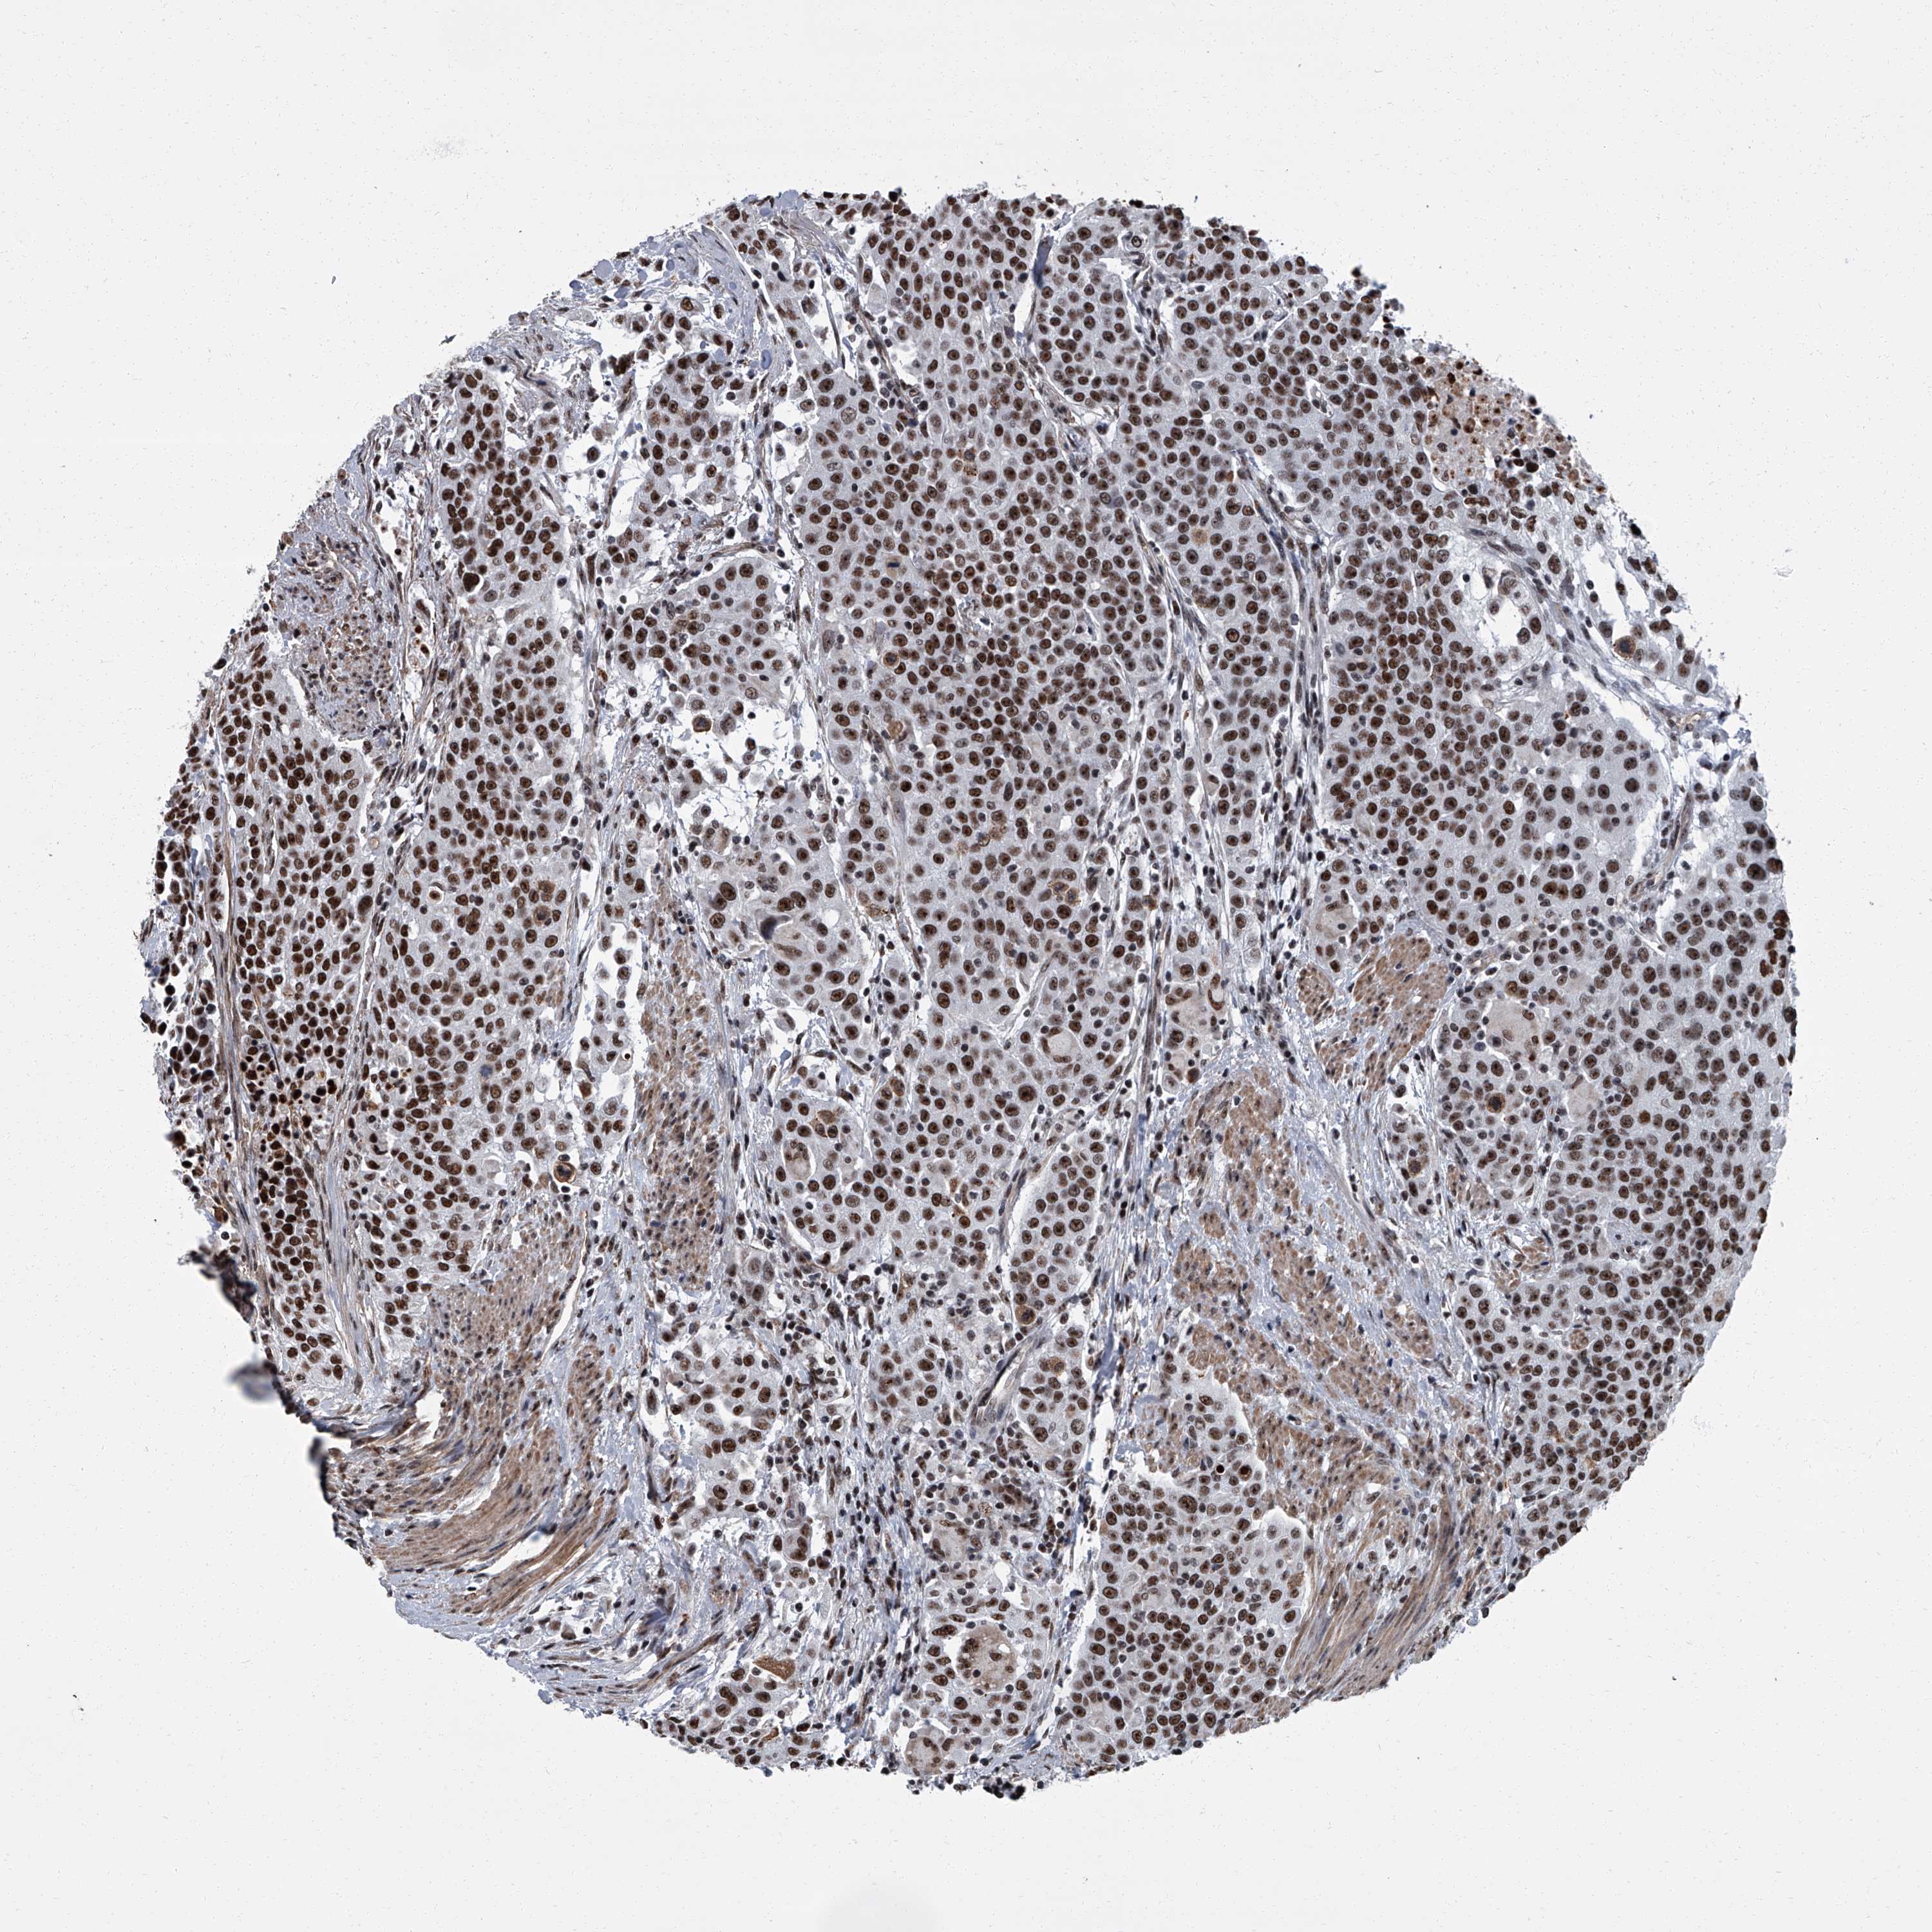

UROTHELIAL CANCER - Protein expressioni

A mouse-over function shows sample information and annotation data. Click on an image to view it in a full screen mode. Samples can be filtered based on level of antibody staining by selecting one or several of the following categories: high, medium, low and not detected. The assay and annotation is described here.

Antibody stainingi

Antibody staining in the annotated cell types in the current human tissue is reported as not detected, low, medium, or high, based on conventional immunohistochemistry profiling in selected tissues. This score is based on the combination of the staining intensity and fraction of stained cells.

Each image is clickable and will lead to virtual microscopy that enables deeper exploration of all samples and also displays staining intensity scores, fraction scores and subcellular localization as well as patient and tissue information for each sample.

Antibody HPA031215

Antibody HPA031216

Urothelial carcinoma, High grade